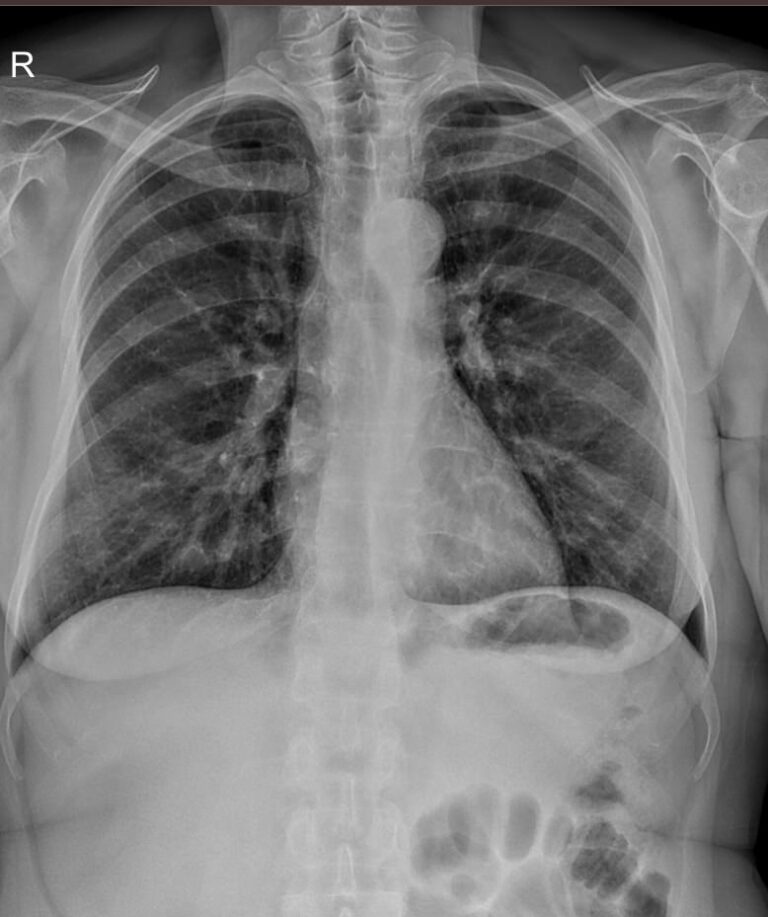

В качестве основного метода исследования при патологии ребер назначают рентгенодиагностику. Это простой и доступный способ узнать состояние костной ткани изнутри, не нарушая целостности кожных покровов. минимальная доза излучения современных рентгеновских аппаратов делает рентгенографию безопасной.

На рентгенограмме будут видны:

• Перелом и его локализация;

• Отек, отломки и осколки кости и инородные тела в мягких тканях;

• При рентгене верхних ребер ― возможные повреждения тканей легких, трахеи, пищевода;

• При обследовании нижних ребер ― повреждение тканей и органов верхней части живота: печени, селезенки, почек, диафрагмы.